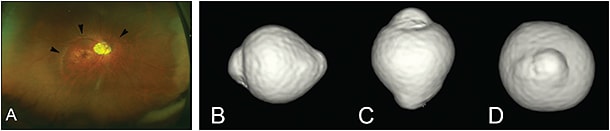

The most common methods to detect staphylomas have been color fundus photography and ultrasonography. Especially, conventional 50° fundus photos are widely used in many epidemiological studies. However, most staphylomas involve wide areas of the fundus (especially the upper and temporal direction), and thus the entire extent of the staphyloma does not fit within the 50° field of view of conventional fundus photographs (Figure 2). Similarly, in most cases, staphylomas are too wide to fit into the length of an OCT scan (Figure 3).

Despite the usefulness of 3D MRI, it is still difficult to perform in a large population of patients in routine clinical settings. It also remains difficult to perform 3D MRI due to availability and cost. As a surrogate, the author and colleagues4,9 used widefield fundus imaging by the Optos system and analyzed the presence of staphyloma by examining pigmentary abnormalities along the upper edge of staphyloma. However, the disadvantage of widefield imaging lies in a lack of 3D information.

To solve these issues, we are conducting ongoing studies using a prototype ultra-widefield OCT by Canon Inc. (Tokyo) in our institute. In the near future, this technique will become a cost-effective and more available tool to evaluate the presence and types of staphyloma. Different from 3D MRI, widefield OCT can also visualize how the retina and optic nerve are damaged by eye deformity (Figure 5). This is important because it can demonstrate the exact cause of vision-threatening complications in pathologic myopia.

Among staphylomas, the wide macular type was by far the most common (74% of all staphylomas) (Figure 8). The narrow macular type followed (14%) (Figure 9). Other types are rare, and they include inferior staphyloma (3%) and nasal staphyloma (2%).